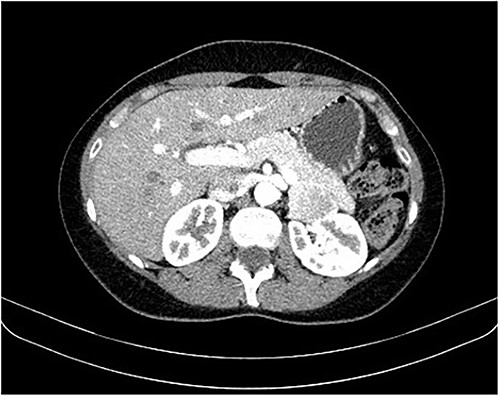

During a screening imaging examination of her liver disease, a lesion suspected of malignancy was detected. The ultrasound disclosed a hypoechoic nodule, vaguely heterogeneous, located in segment VII, subcapsular, and with ~22 mm in diameter (Fig. 1). Liver blood tests and serum alpha-fetoprotein level were normal. For better characterization, a CT scan was performed. The CT showed, in addition to signs of chronic liver disease, the presence of a solid subcapsular nodule of segment VII, measuring 23 mm, with hypervascular behavior in the arterial phase (Fig. 2) and washout in late venous phase (Fig. 3).

CT scan showing the same mass as shown in Fig. 2 but with washout in the portal venous phase.